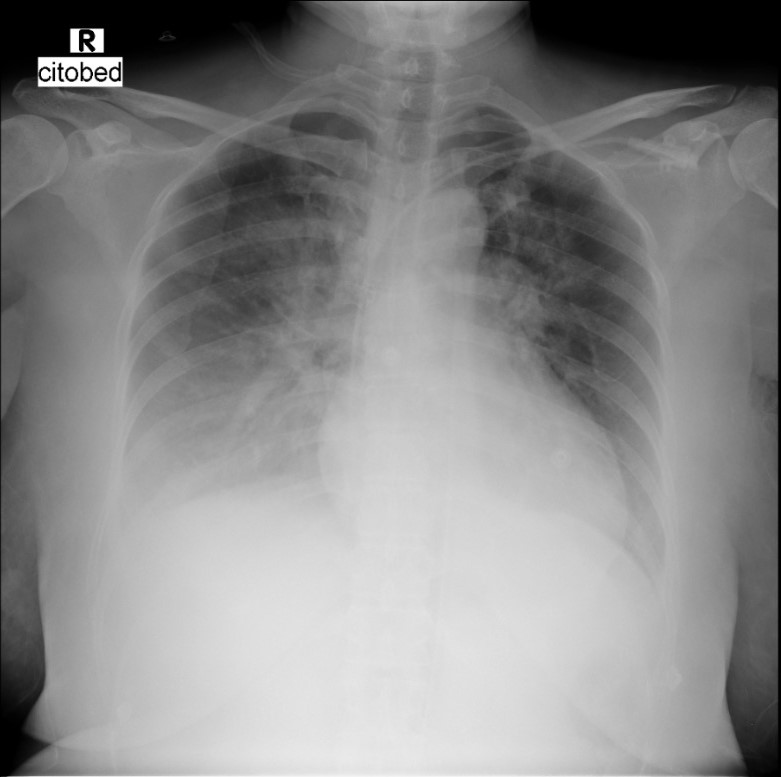

A 51-year-old woman with a history of type 2 DM was referred to our hospital with sudden onset of chest pain and shortness of breath. She had been hospitalized the day before with fever, nausea, and diarrhea. Prior to transfer, her condition deteriorated into cardiogenic shock with acute heart failure for which norepinephrine, dopamine, furosemide, and oxygen via NRM was administered. Upon arrival, her blood pressure was 80/40 mmHg, CRT > 3 seconds, and bilateral crackles were heard.

At the onset of chest pain, her electrocardiogram (ECG) showed total AV block and serial ECG showed QRS and ST-T changes. New onset Left Bundle Branch Block (LBBB) and ST-elevation was found in the inferior and anterior leads. Laboratory tests revealed elevated troponin levels consistent with acute STEMI and a positive IgM Salmonella Typhi (TUBEX) test.She had received a loading dose of dual antiplatelet therapy, fondaparinux, and ceftriaxone in the previous hospital.

Based on the clinical presentation, ECG, and laboratory results, the initial working diagnosis was Anterior STEMI with KILLIP Class IV. CAG was then performed via radial artery using a 6-French introducer sheath, revealing no significant stenosis in the coronary arteries. As the cardiogenic shock still persisted despite optimal inotrope and vasopressor, an IABP was then inserted via femoral artery with the initial setting of 1:2 assist ratio. She was then transferred to the intensive care unit (ICU) where bedside echocardiography revealed a left ventricular ejection fraction (LVEF) of 48% without regional wall motion abnormalities, supporting a non-ischemic etiology. During hospitalization the patient developed acute kidney injury (AKI) with anuria. Further workup for myocarditis showed elevated C-reactive protein (CRP), high procalcitonin levels, and metabolic acidosis. Blood culture was sterile as she had been given antibiotic before. Given rapid clinical deterioration, broad-spectrum antibiotics (meropenem and cefoperazone) were initiated, and hemodialysis was performed. Her condition steadily improved throughout treatment. The IABP was successfully weaned off after four days, and inotropes were gradually tapered off. Serial ECGs also showed gradual resolution of the ST segment elevation and LBBB. After ten days of optimal antibiotics treatment, she continued to improve and was safely discharged from the hospital.